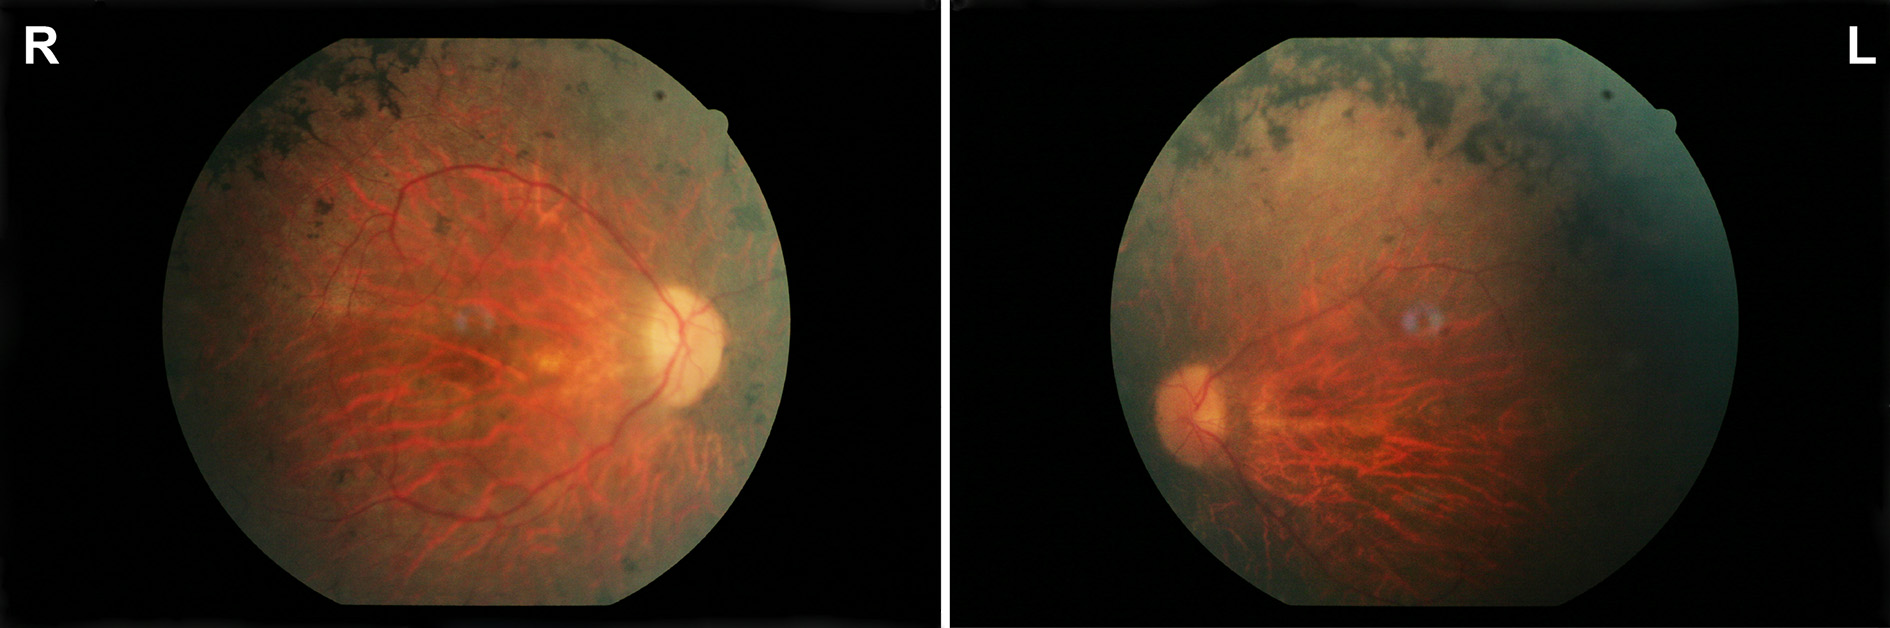

Figure 1 of Zobor, Mol Vis 2014; 20:178-182.

Figure 1. Morphological findings. Fundus pictures of the right (R) and left eye (L) of the index patient showing pallor optic discs, attenuated vessels, and characteristic pigment changes in the mid-periphery.